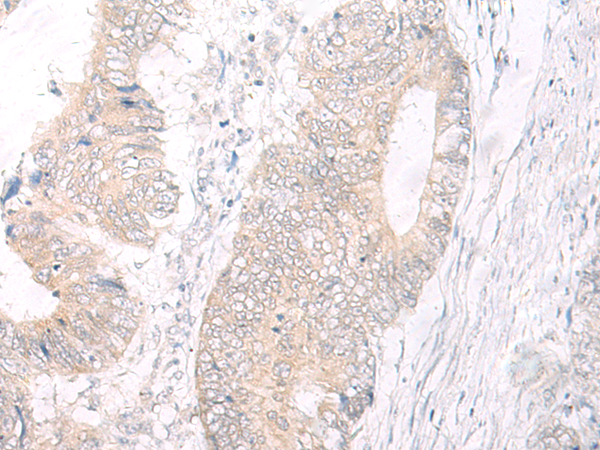

分类: 科研抗体货号: P06438别名: ENT2; DER12; HNP36应用: WB,IHC反应种属: Human